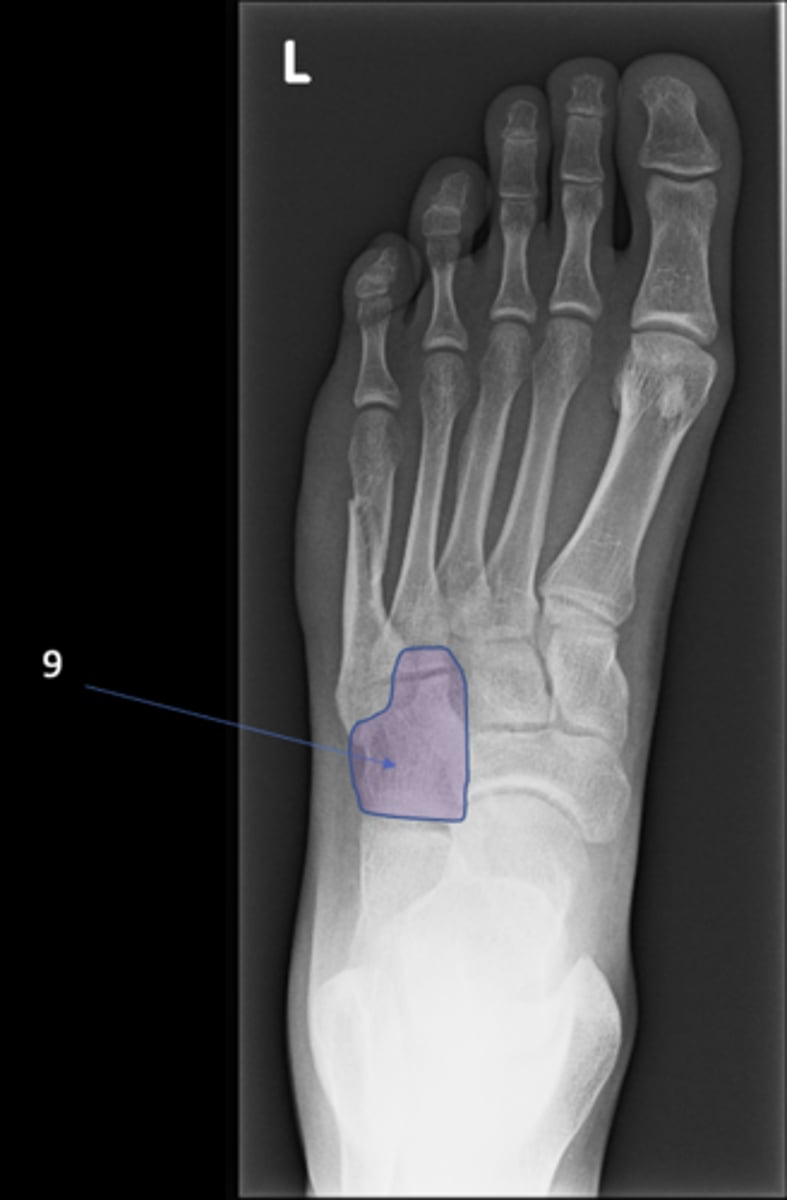

99

New cards

Cuboid

ID 9

<p>ID 9</p>

100

Base of 5th metatarsal

ID 10

<p>ID 10</p>